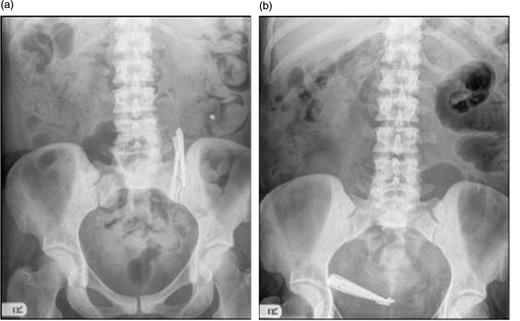

Our patient presented with a 4-day history of generalized abdominal pain, vomiting and absolute constipation on a background of intermittent episodes of faecal impaction. This presentation fell between regular abdominal X-ray follow-up for a known intestinal foreign body, which had been static in the proximal ileum for 5 years (Fig. 1a). Subsequent examination revealed a diffusely tender abdomen with distension.

(a) Foreign bodies remain static in the small intestine on follow-up. (b) Foreign bodies seen to have moved to overlie the right iliac fossa.

A full blood examination revealed a mild iron deficiency anaemia (which the ingested scissors failed to medicate), but was otherwise normal. Abdominal X-ray demonstrated the expected: the known foreign body was no longer found in the left upper quadrant but instead occupied the right iliac fossa in the caecal cul-de-sac (Fig. 1b), with small bowel loop dilation. Erect chest X-ray confirmed the absence of free gas. Subsequent abdominal computer tomography highlighted the foreign body present in the distal ileum causing obstruction.